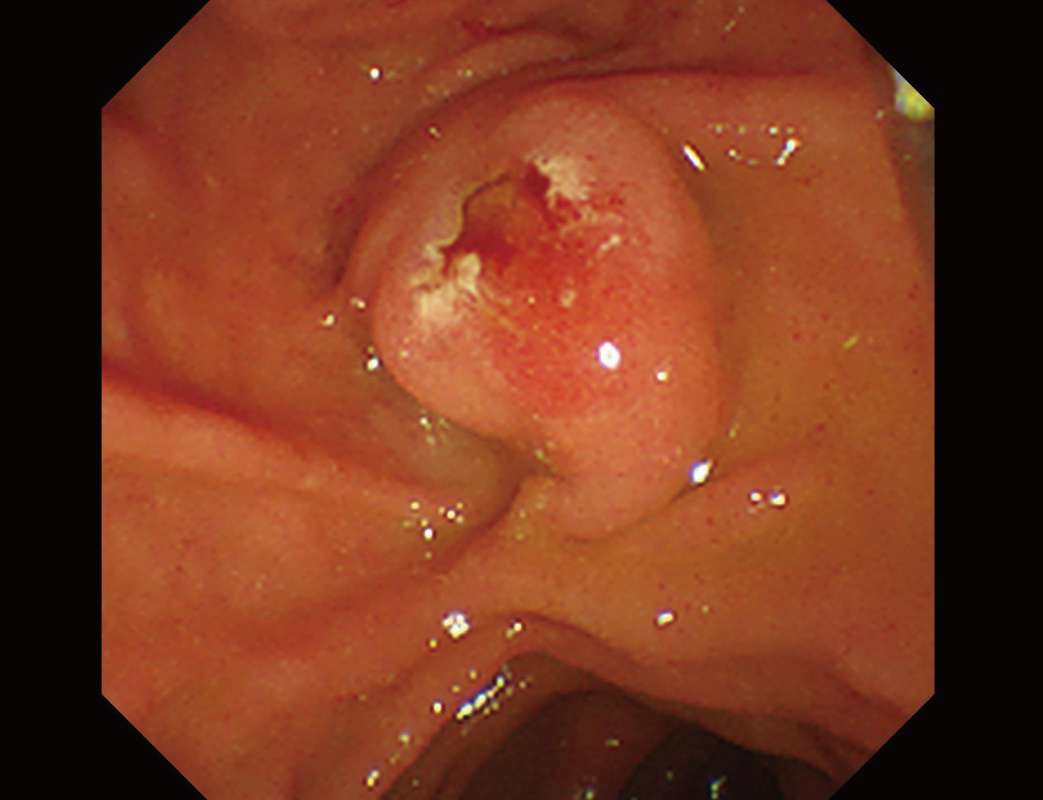

症例

1. S状結腸の有茎性ポリープです。